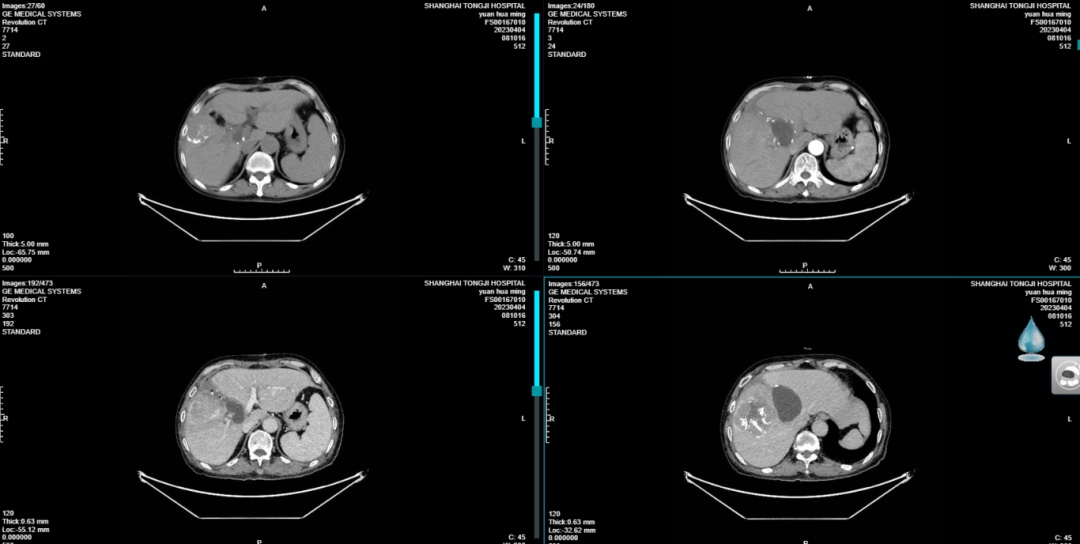

ALPPS二期手术前CT图